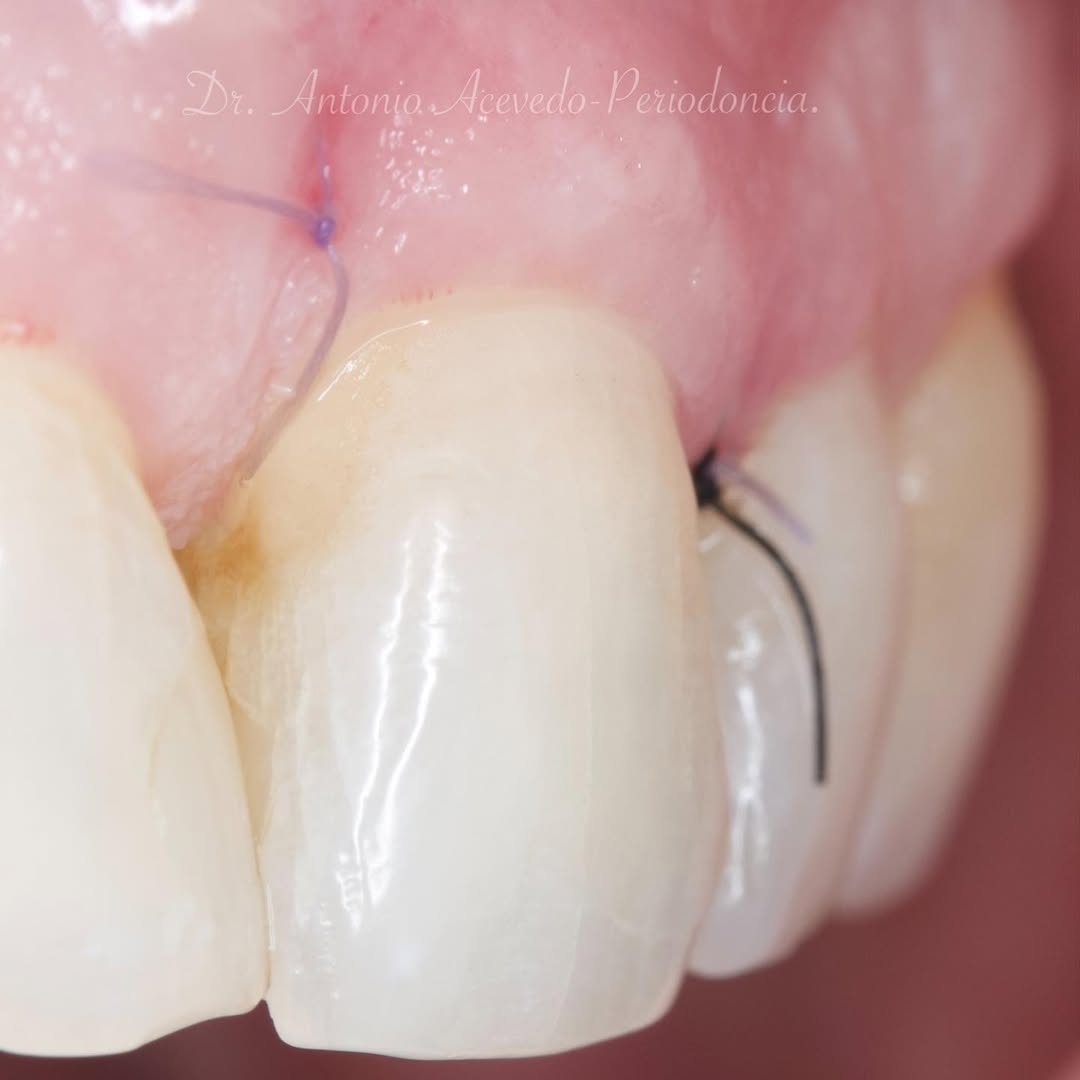

Durante una mañana, asistirás a una Cirugía Mucogingival de recubrimiento radicular de una recesión unitaria en 31 con frenillo asociado. Gracias al uso del microscopio y a la proyección en tiempo real en pantalla, verás exactamente lo mismo que veo yo durante la cirugía, sin tener que estar

Se realizará todo el procedimiento con un microscopio operatorio, lo que permite al alumno ver toda la cirugía en directo en una pantalla en la sala de cirugía.

Gracias al uso del microscopio y a la proyección en tiempo real en pantalla, verás exactamente lo mismo que veo yo durante la cirugía, sin tener que estar